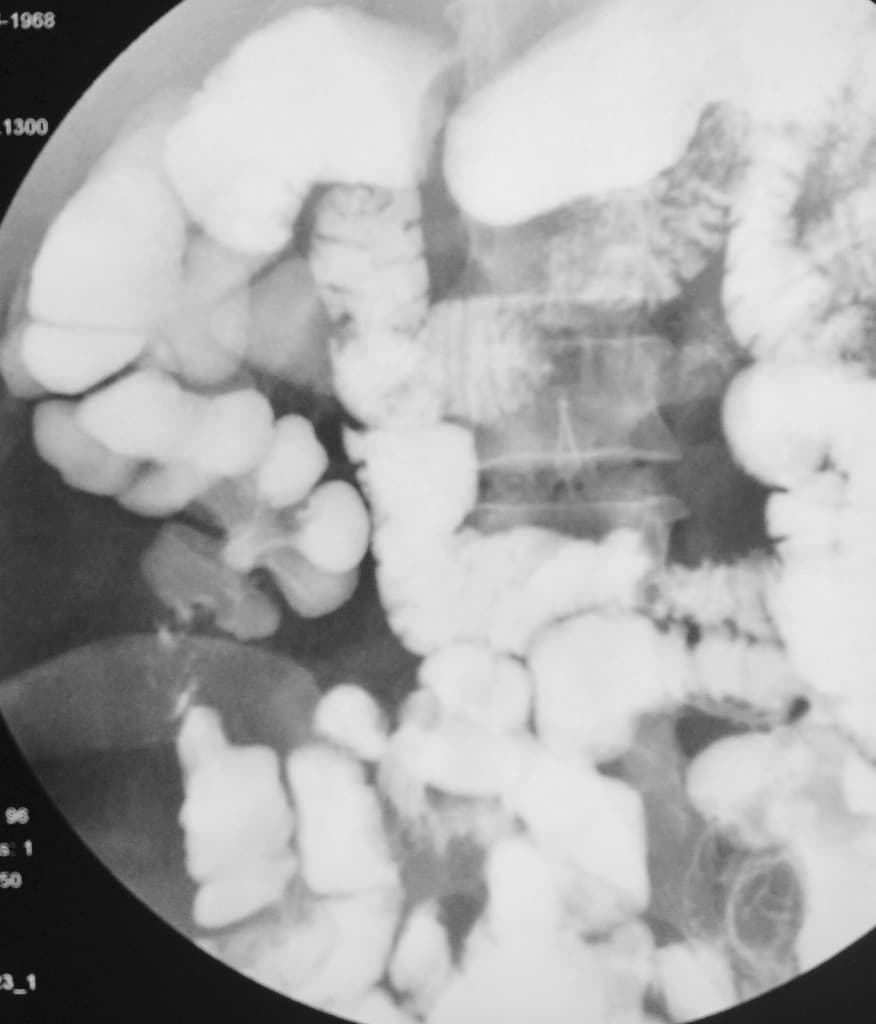

J-pouch procedure - Crohn disease

Ileocecal tuberculosis